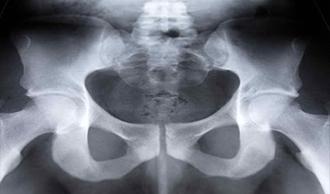

articulaciones sacro-ilíacas

Las articulaciones sacro-iliacas están situadas a ambos lados de la parte inferior de la columna. Unen la base de la columna (sacrum) con la pelvis (ilium). Las articulaciones sacro-iliacas proporcionan estabilidad y actúan como amortiguadores cuando caminamos o corremos. Las articulaciones sacro-iliacas pueden inflamarse o dañarse y provocar dolor en la parte inferior de la espalda.